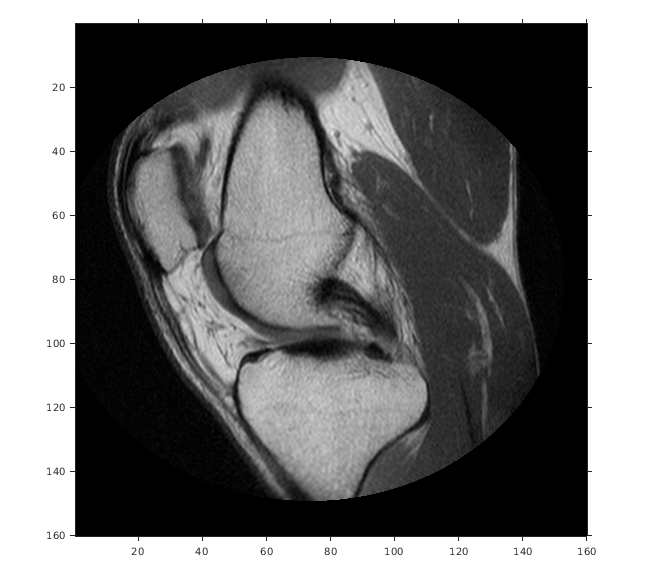

Считайте 2D полутоновое изображение колена в рабочую область.

Отобразите изображение, включая пространственный объект привязки. Координаты осей отражают мировые координаты. Заметьте, что координата (0,0) находится в левом верхнем углу.

imshow(A,RA,'DisplayRange',[0 512])

Figure contains an axes object. The axes object contains an object of type image.